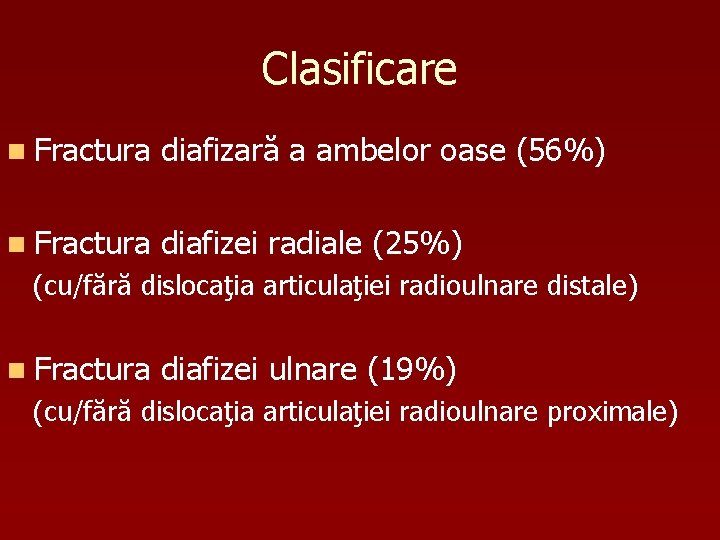

Clasificare n Fractura diafizar a ambelor oase 56

Clasificare n Fractura diafizară a ambelor oase (56%) n Fractura diafizei radiale (25%) (cu/fără dislocaţia articulaţiei radioulnare distale) n Fractura diafizei ulnare (19%) (cu/fără dislocaţia articulaţiei radioulnare proximale)